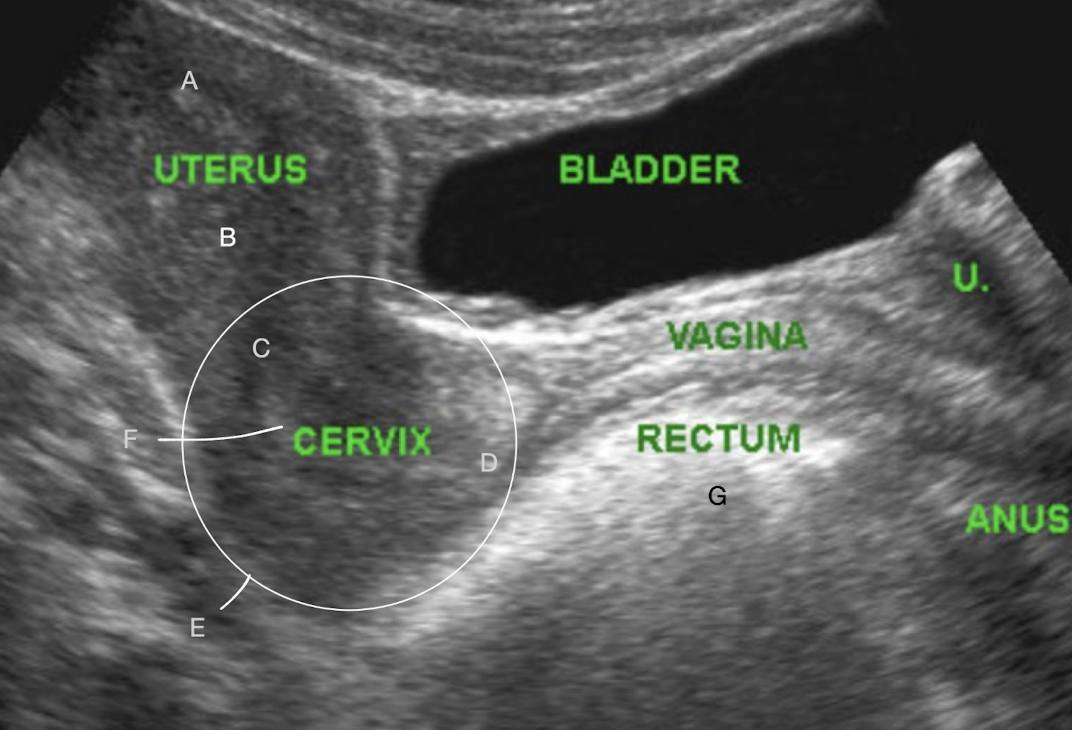

SONO: vagina, cervix, uterus

A?

fundus

B?

body

C?

internal os

D?

external os

E?

LUS

F?

cervical canal

G?

bowel